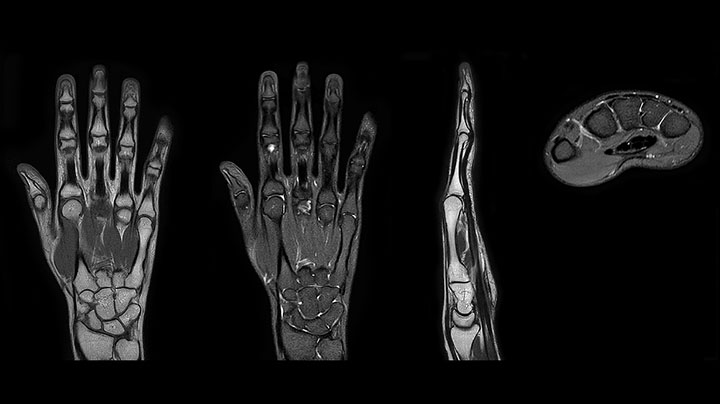

Bildgebung der Hand mit Prodiva deckt die Fingerspitzen und das gesamte Handgelenk ab. Die dS MSK M Spule ist anwenderfreundlich.

Scandauer: 2:55 Minuten, FOV: 160 mm, erfasste Voxel: 0,55 x 0,83 x 3,0 mm.

Scandauer: 04:19 Minuten, FOV: 160 mm, erfasste Voxel: 0,55 x 0,80 x 3,0 mm.

Scandauer: 02:50 Minuten, FOV: 160 mm, erfasste Voxel: 0,70 x 0,99 x 3,0 mm.